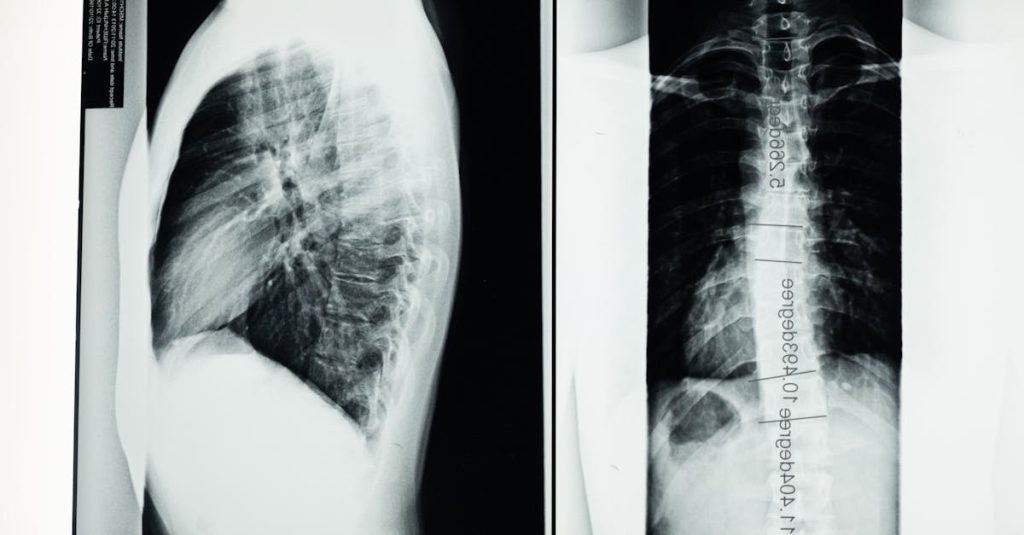

Quels examens sont nécessaires avant de commencer un traitement de décompression pour une protrusion discale?

Une IRM ou une radiographie est généralement recommandée pour évaluer l’état de la colonne vertébrale.